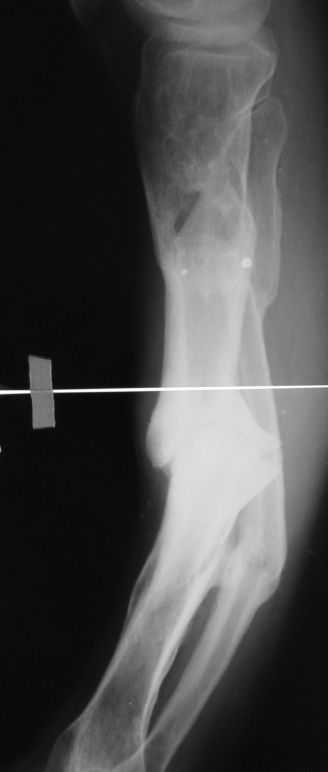

Уважаемые коллеги. Имеется вот такой псевдоартроз.

Планируем БИОС tibia стержнем Chm, остеотомию малоберцовой и большеберцовой через зону псевдоартроза. Вопрос! Коррекцию лучше сделать одномоментно во время операции или дозированно в аппарате недели за 2-3, а потом nailing? И ещё делать нормо или с учетом вальгуса гиперкоррекцию?